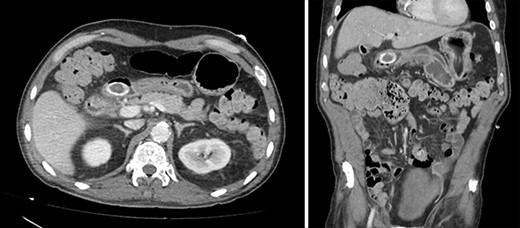

Contrast-enhanced CT. Axial and coronal views of a 4 cm stone in the duodenal bulb, gastric dilation, and pneumobilia in the operative patient.